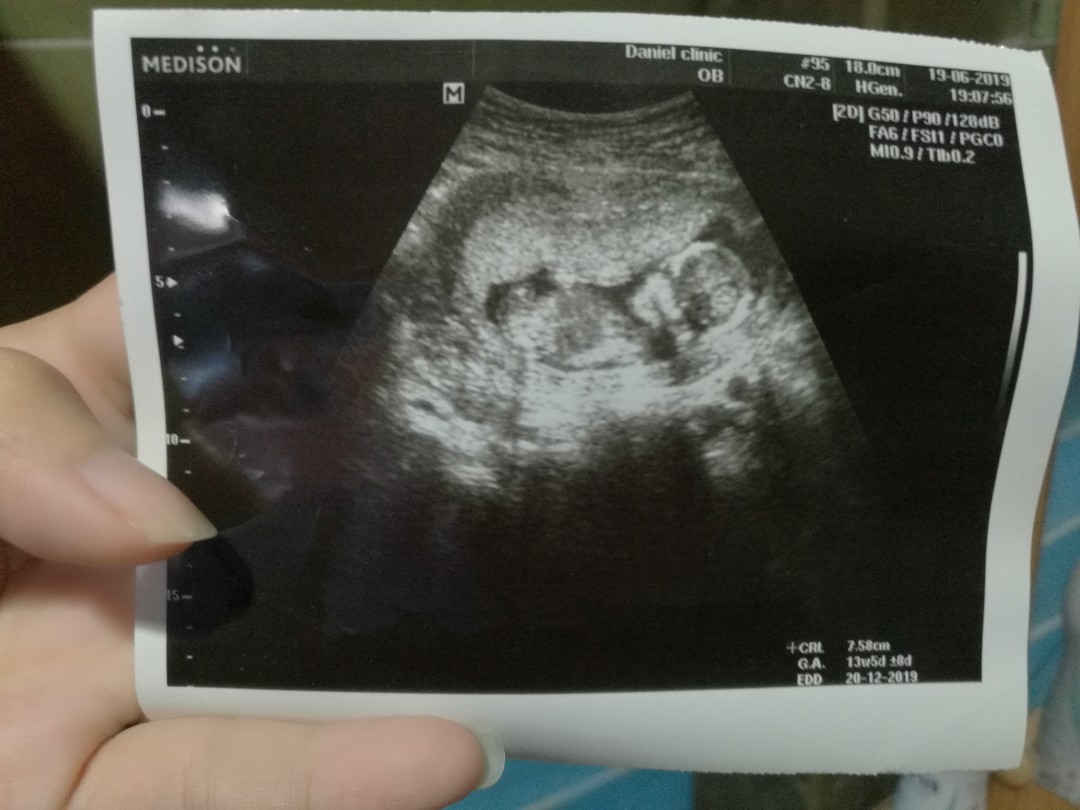

13w5dค่ะ